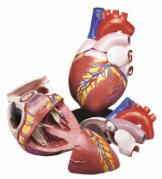

| Human Body Circulatory System -

| The muscular heart

pumps blood out through tubes or vessels, called arteries. These

branch repeatedly into microscopic capillaries that joint to form veins

that carry the blood back to heart. Our anatomical models begin

with an overview of the Circulatory System and even include functional

models. Next comes the arteries that carry the blood. The

bulk of the pages are on the Human Heart. The Starter Hearts vary

considerably, ranging from simple ones suitable for elementary education

to more advanced models. The pages that follow portray

increasingly detailed models, including many suitable for advanced

medical school education. These are suitable for internal medicine

and the study of cardiovascular diseases.